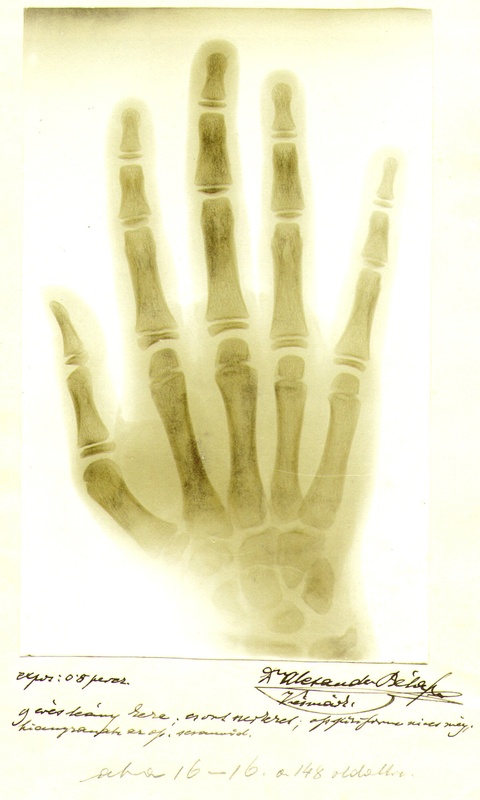

Nedal sa odradiť prvými neúspechmi, desať i stokrát opakoval svoje pokusy, len aby sa dopátral pravdy. Túžil, aby sa potvrdilo, že to, čo robí má zmysel. Veril, že všetko vynaložené úsilie napokon pomôže chorému človeku, spresní diagnózu, urýchli i zlepší celý liečebný postup. Neúnavnými experimentmi, pokusným snímkovaním rôznych predmetov, rastlín, kvetov, drobných živočíchov a neskôr častí ľudského tela dospel k zhotoveniu technicky a fotograficky kvalitných kontrastných a verných snímok. Na nich ako prvý na svete odborne vysvetľoval schopnosť röntgenového obrazu poskytnúť aj predstavu hĺbky. Tento jav nazval „plastikou röntgenového obrazu“. Podľa toho vypracoval metodiku tzv. plastického snímkovania a založil plastickú röntgenológiu, v čom mu patrí priekopnícke svetové uznanie. Plastické obrazy vyhotovoval tak, že najprv urobil snímku mäkkými, a potom tvrdými X lúčmi, dvakrát exponoval, a keď potom obe kópie priložil na seba, získal tretiu, až napokon aj pozitívny obraz, ktorý vzbudzoval priestorový dojem.

Vo svojej skromnej ordinácii vidieckeho lekára zriadil v roku 1897 prvé rádiodiagnostické pracovisko na Slovensku, kde sa X lúče začali používať v skiagrafii a postupne aj pri skiaskopii, teda pri vyšetrovaní chorých pomocou röntgenových snímok a presvietením. Sklenené fotografické dosky primitívneho röntgenu sa museli pred použitím najskôr v tme zabaliť do čierneho papiera a poriadne, starostlivo prelepiť. Vyvolávanie, ustaľovanie a umývanie snímok sa robilo v noci, sušenie vo dne. Cez deň si plnil všetky povinnosti praktického lekára a zvyšný čas trávil nad pokusmi s X lúčmi.

Z praktického vidieckeho lekára a provinčného röntgenológa sa vypracoval až na vysokoškolského učiteľa. Jeho cesta viedla cez všestrannú lekársku činnosť praktického lekára a chirurga malej improvizovanej nemocnice, cez individuálne experimentovanie a vedeckovýskumnú činnosť na poli röntgenológie, až po klinickú röntgenodiagnostiku a pedagogickú činnosť na najvyššej odbornej úrovni. O svojich výskumoch publikoval 59 vedeckých prác a referoval o nich na zasadnutiach Spolku uhorských lekárov v Budapešti, kde prednášal o osifikácii kostí, čo dokumentoval svojimi snímkami. Výsledky svojej bádateľskej práce zverejnil vo vyše 110 odborných prácach a prednáškach na mnohých svetových kongresoch ─ Amsterdam, Berlín, Zürich, Mníchov, Kluž, Miškovec, Odesa, Veszprém a i. Jeho štúdie o röntgenologickej problematike boli publikované v nemeckých i anglických odborných časopisoch, časopisecké a knižné diela vychádzali na Slovensku, v Uhorsku a Rakúsku, v Nemecku, Švajčiarsku, Anglicku a v Spojených štátoch amerických.

Dňa 22. 7. 1914 Dr. V. Alexandra profesorský zbor budapeštianskej univerzity zvolil za riadneho profesora röntgenológie a rádiológie. V tom období sa začínajú uňho objavovať nežiadúce účinky X lúčov, na prstoch rúk sa začínajú objavovať príznaky radiačného poškodenia, typické kožné zmeny svedčiace o chronickej dermatitíde s tvorbou ložísk hyperkeratóz. Nasledovala častá únava bolesti hlavy a svalstva, vysoké teploty.

Unikátny prvý röntgenový prístroj sa zachoval do dnešných dní a je spolu s ukážkami pôvodných snímok súčasťou expozície na Kežmarskom hrade. .